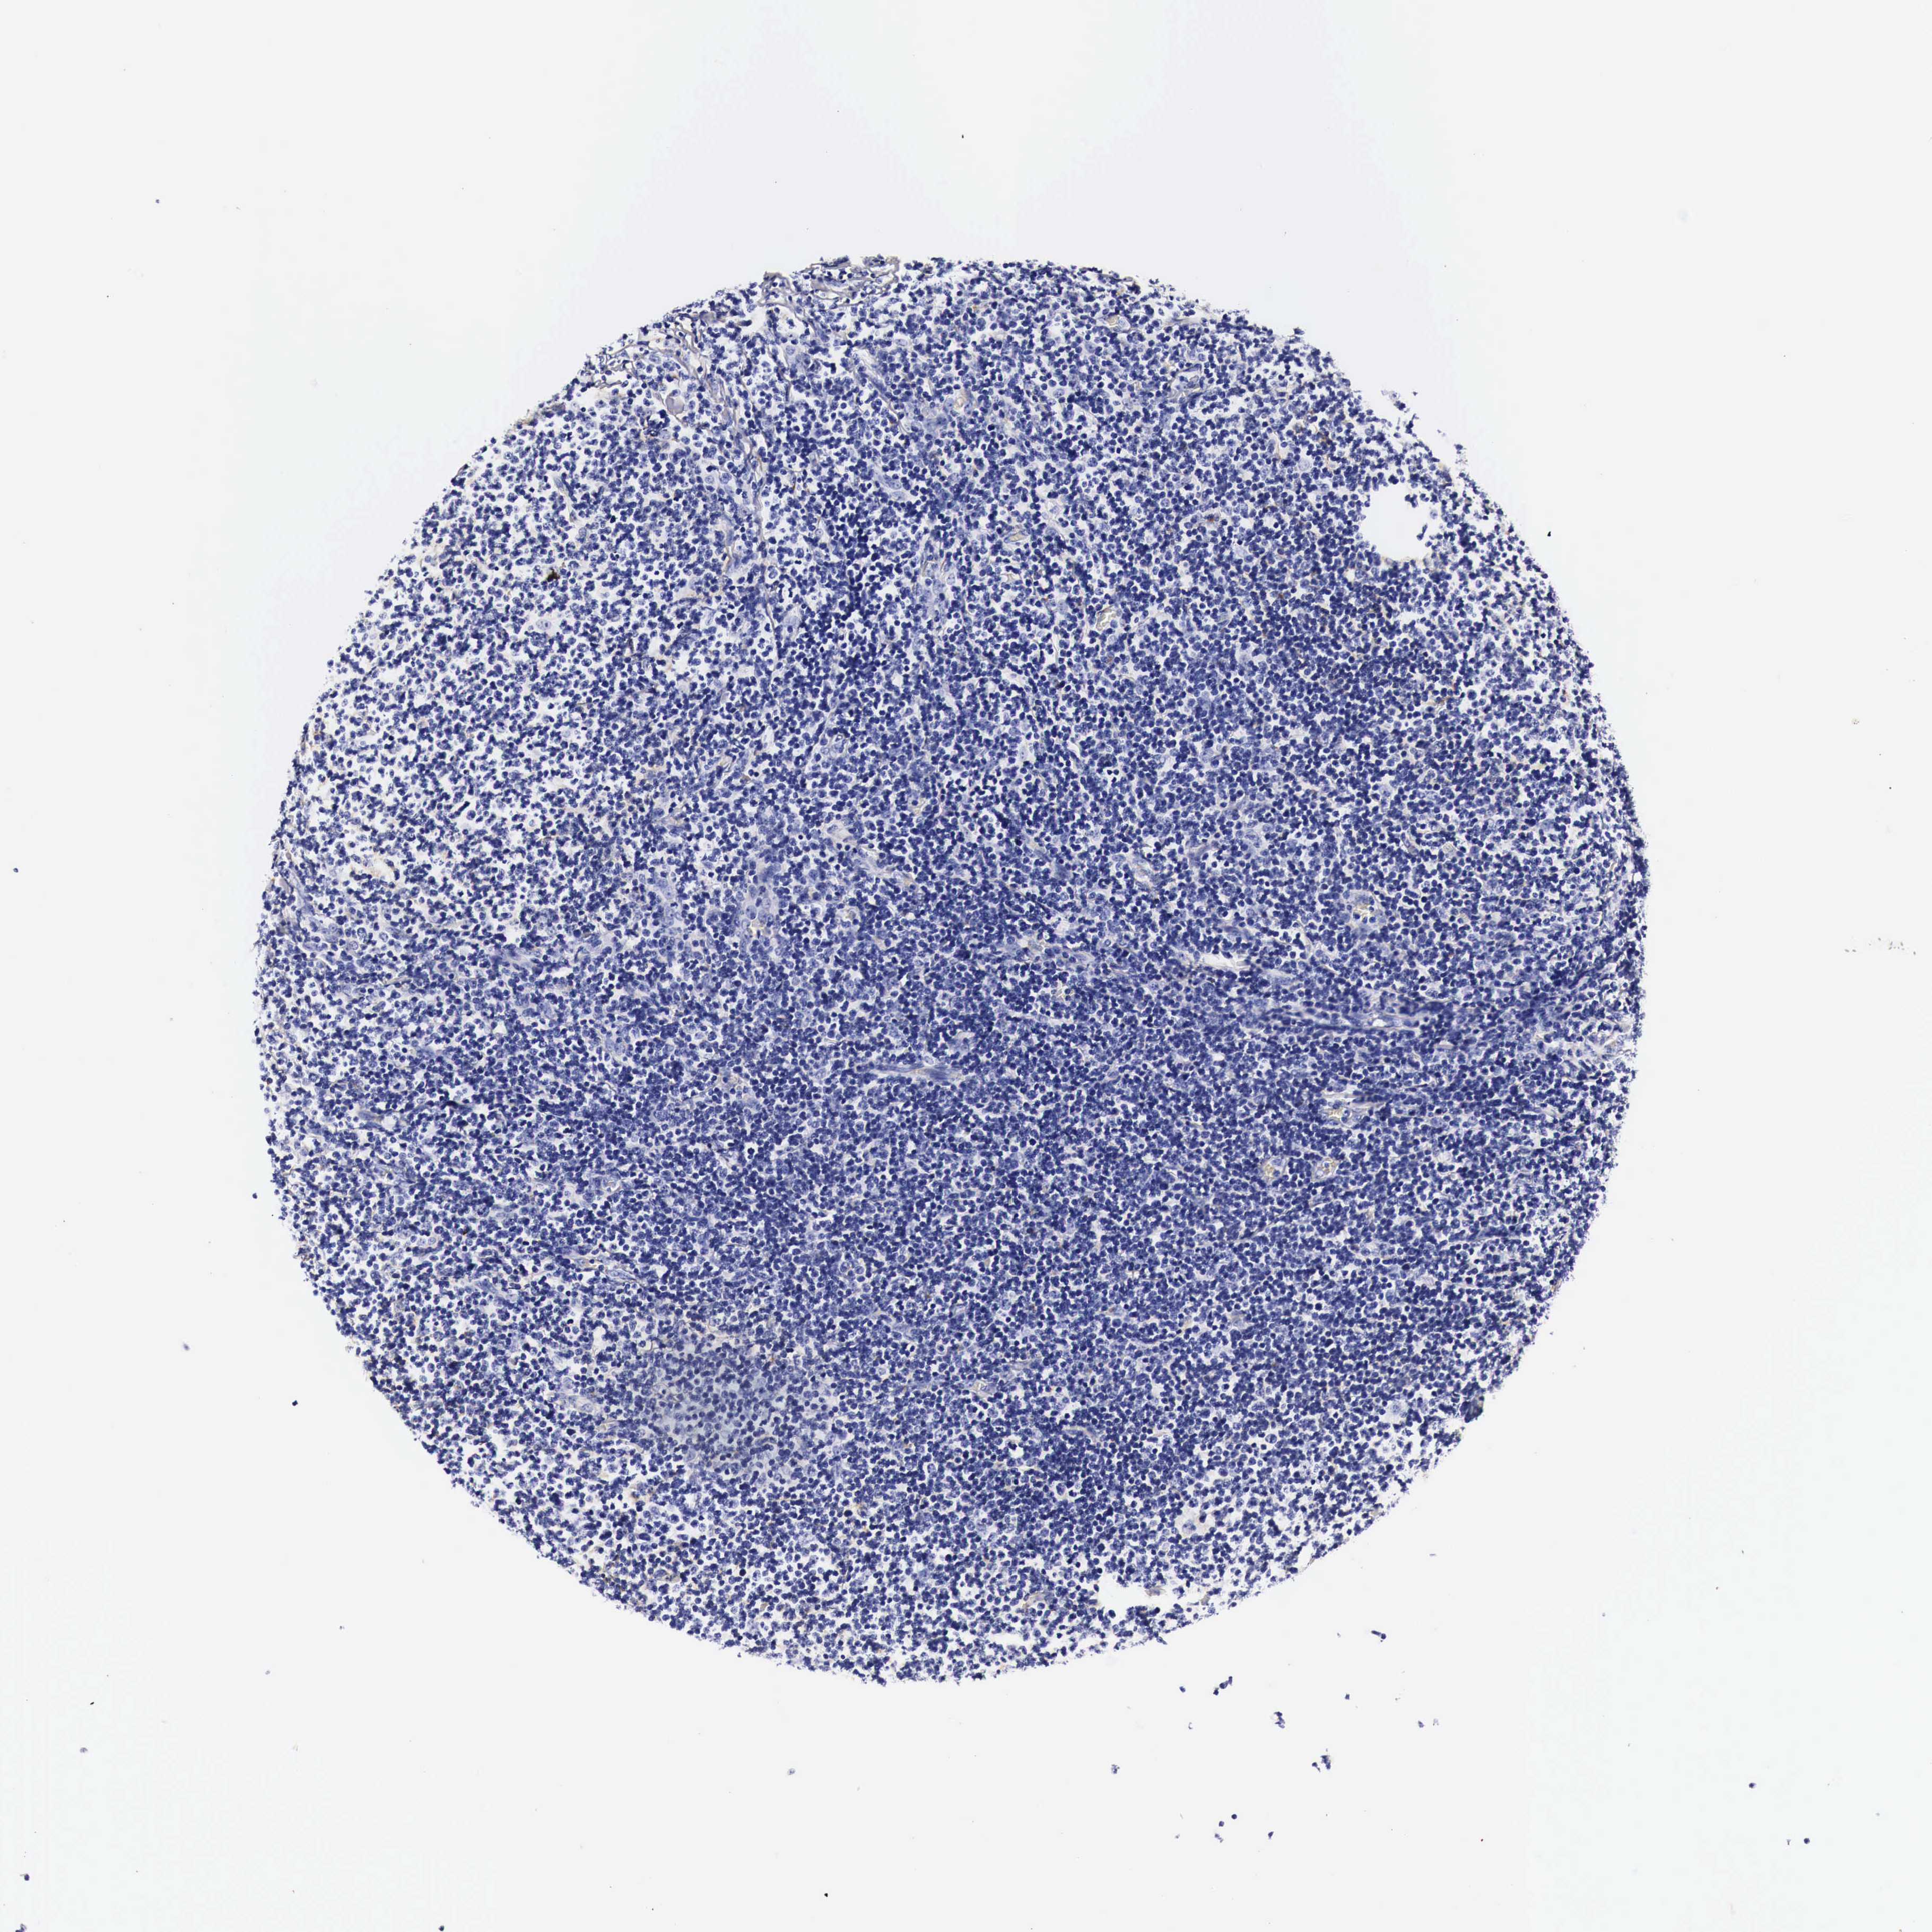

LYMPHOMA - Protein expressioni

A mouse-over function shows sample information and annotation data. Click on an image to view it in a full screen mode. Samples can be filtered based on level of antibody staining by selecting one or several of the following categories: high, medium, low and not detected. The assay and annotation is described here.

Antibody stainingi

Antibody staining in the annotated cell types in the current human tissue is reported as not detected, low, medium, or high, based on conventional immunohistochemistry profiling in selected tissues. This score is based on the combination of the staining intensity and fraction of stained cells.

Each image is clickable and will lead to virtual microscopy that enables deeper exploration of all samples and also displays staining intensity scores, fraction scores and subcellular localization as well as patient and tissue information for each sample.

Malignant lymphoma, non-Hodgkin's type, High grade

Hodgkin's disease, NOS

Malignant lymphoma, non-Hodgkin's type, Low grade